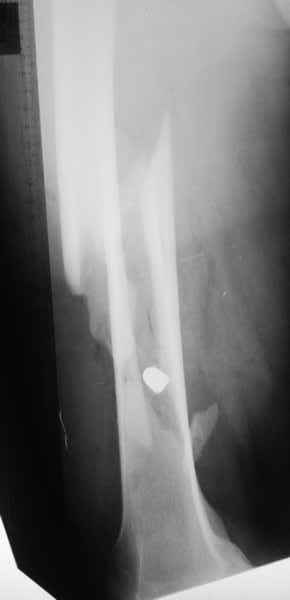

Больной 27 лет поступил 22.06.2010 по поводу огнестрельного пулевого слепого ранения правого бедра на границе средней и нижней трети

с огнестрельным косым оскольчатым переломом правой бедренной кости со смещением отломков(снимок передняя проекция).Больной 110 кг рост 176 см.Гемодинамически стабилен, показатели крови в норме.

По передне-внутренней поверхности правого бедра в средней трети имеется рана округлой формы диаметром 1 см.на данный момент состояние удовлетворительное, признаков воспаления нет. Планируется на 10 сутки аппарат внешней фиксации(спице-стержневой) или накостный металлоостеосинтез.